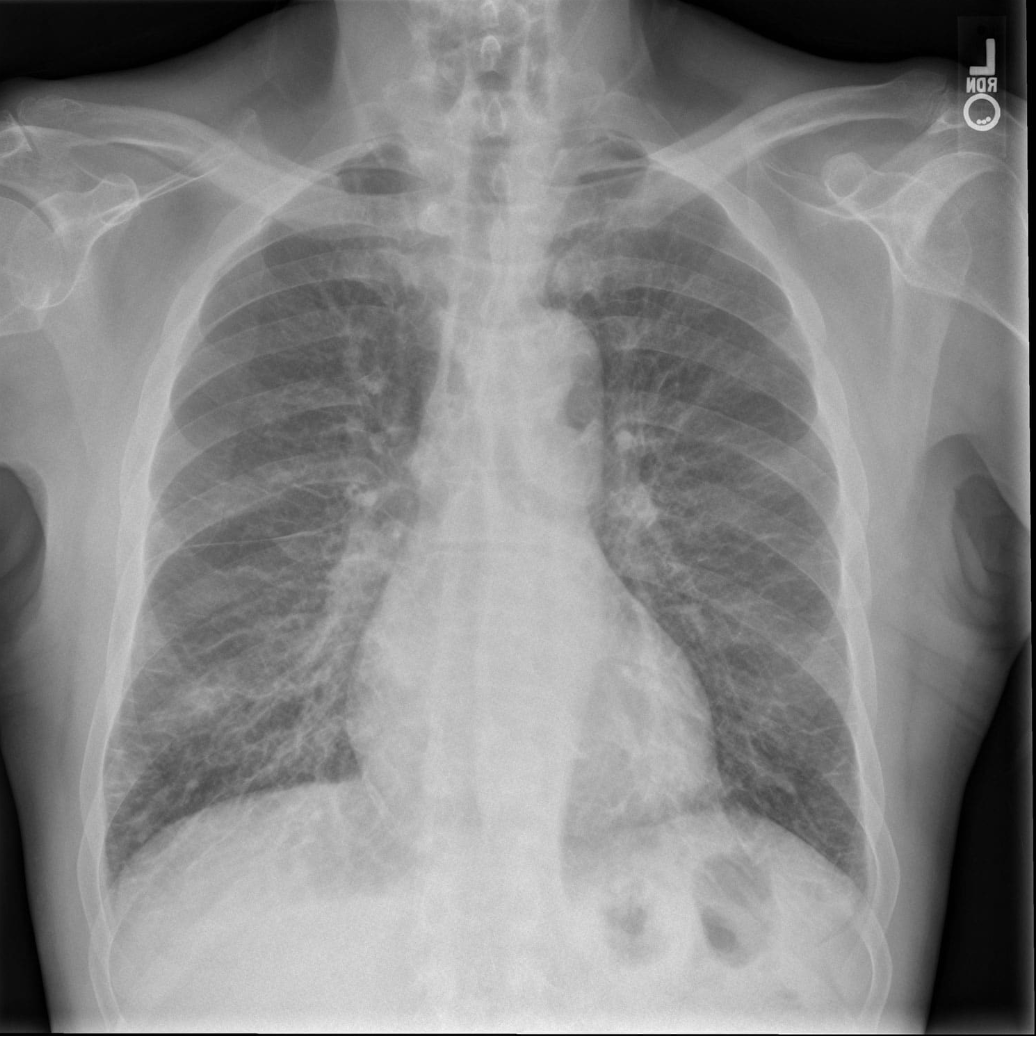

Answer: Sarcoidosis

Sarcoidosis is characterised by bilateral hilar adenopathy and certain clinical features such as erythema nodosum. Diagnosis is made in consideration of the clinical picture and CXR, alongside the gold-standard diagnostic tool of bronchoscopic biopsy which would show non-caseating granulomas with giant cells, asteroid bodies, and Schaumann bodies.